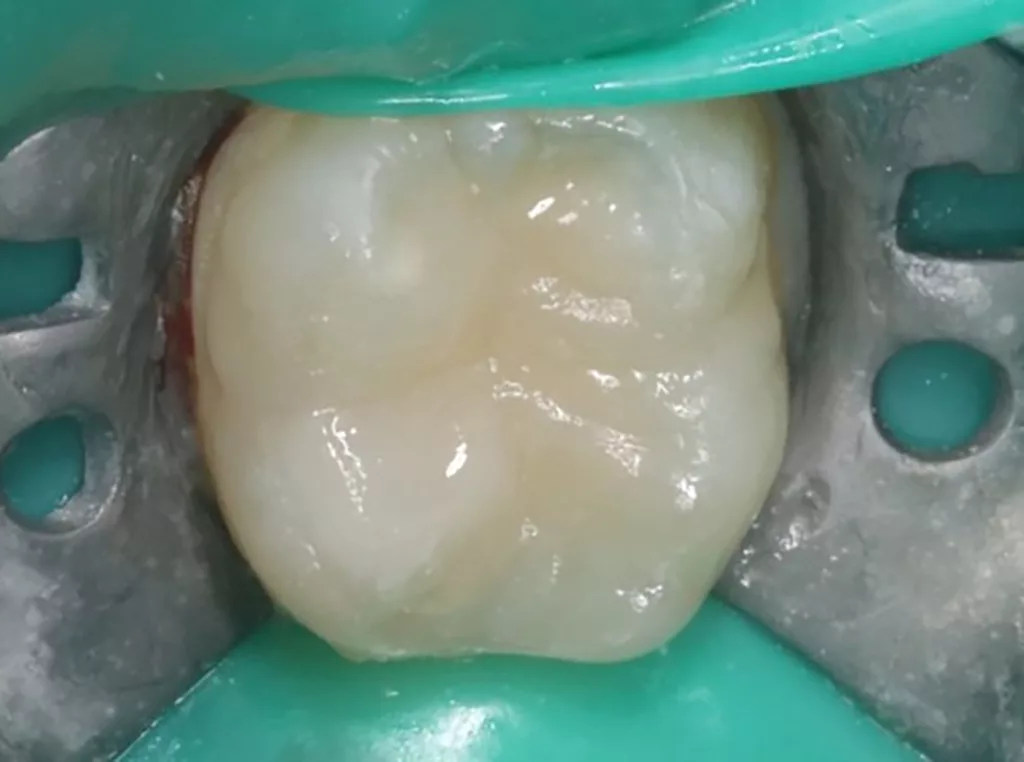

V. Slabkovskyi, O. Liutikovwährend des Durchbruchs des Zahnes 36.

Das fünfjährige Mädchen stellte sich 2017 zur jährlichen Routinekontrolle vor. Im Rahmen der Untersuchung wurden Röntgenaufnahmen der Milchmolaren gemacht (Abb. 2). Der klinische und radiologische Befund der vor uns früher gelegten Kompositfüllungen war gut, es wurde allerdings eine PEIR an den noch nicht durchgebrochenen ersten bleibenden Molaren festgestellt (Abb. 2). Den Eltern wurde empfohlen, sich unverzüglich bei Beginn des Durchbruchs der ersten Molaren erneut zur Behandlung vorzustellen. Ein Jahr später erschien die junge Patientin schmerzfrei zur Kontrolle. Der Zahn 36 war noch teilweise mit Gingiva bedeckt. Auf einer neuen Röntgenaufnahme (Abb. 1) wurde die PEIR-Läsion mit unveränderter Größe in pulpanahen Bereichen bestätigt (Grad 3 der Läsion nach Seow). Der Zahnschmelz sah intakt aus, es konnte kein pathologischer periapikaler Befund bei den noch nicht ausgewachsenen Zahnwurzeln festgestellt werden. Daraufhin wurden die verschiedenen Behandlungsmöglichkeiten von Fissurenversiegelung bis Vitalerhaltung der Zahnpulpa mit den Eltern des Kindes besprochen.